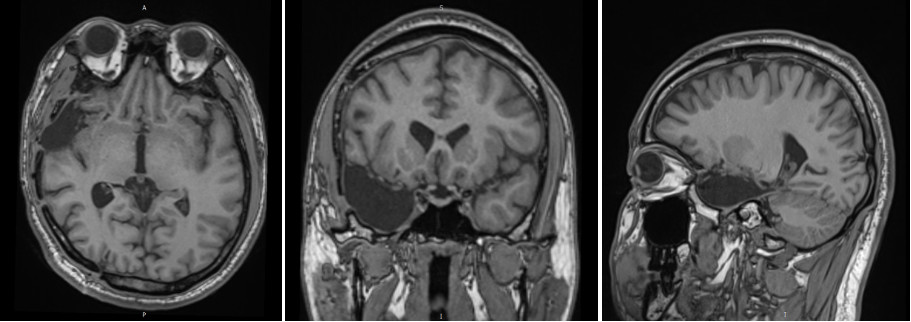

图3. 头颅MRI提示右侧颞极囊状病灶,周围异常信号。

图4. 头颅增强MRI提示右侧颞极囊状病灶周边点状增强。

男性患者,29岁,10首发,癫痫病史19年,十年前曾在外院行右侧颅内电极置入,后因无法定位癫痫病灶,拔出电极未手术,行右侧颞区γ刀治疗一次。入院前发作形式:先兆(难以描述的感觉,之后有凄凉感)→双手重复动作→左上肢屈曲上抬,左手兰花指样后握拳,右手摸索拍打,行为异常(四处乱走),每次1分钟,1次/周。头皮脑电图癫痫放电主要集中在右侧半球,颞区著。头部CT右侧颞叶有低密度改变,周围有散在钙化,头部MRI右侧颞前叶及颞叶内侧结构有异常信号,PET-CT提示右侧颞前叶、内侧结构、岛叶有低代谢。根据术前发作临床症状学、脑电图、影像学、功能影像学结果,考虑右侧边缘系统为致痫病变可能,颞叶内侧结构为主,对侧海马需鉴别,需要通过立体定向脑电图确认致痫区及其范围。用ROSA做了右侧颞区为主的双侧颅内电极置入。颅内电极监测结果发作间期癫痫放电和发作期起源主要在右侧颞叶内侧结构(右侧海马杏仁核),结合临床症状学及影像学、功能影像及颅内电极监测的结果,我们设计了右侧颞前叶及杏仁核、海马全段、岛叶前下部的切除方案,手术过程顺利,术后随访一年无发作及先兆。该患者10年前外院做过一次颅内电极置入及伽马刀治疗,对我们影像学的阅读增加了一些干扰因素,患者术后病理为海绵状血管瘤,按照国际抗癫痫联盟2011年的癫痫病理分类应该属于FCDⅢC型,病变核心区周围的脑皮层可能有发育异常,我们没有分区域做病理检查,只有对病变的核心区域做了病理检查。该患者影像学异常主要集中在颞前叶,患者发作的临床症状学主要边缘系统(颞叶内侧结构)的发作,最后颅内电极也证实了,发作间期异常癫痫放电及发作期起源均来自于颞叶内侧结构,所以我们最后做了颞前叶及内侧结构的切除,如果单看影像学只切除颞前叶病变效果肯定不好。颅内电极在该患者治疗中,为我们验证了致痫区及决定切除范围起到了很重要的作用。